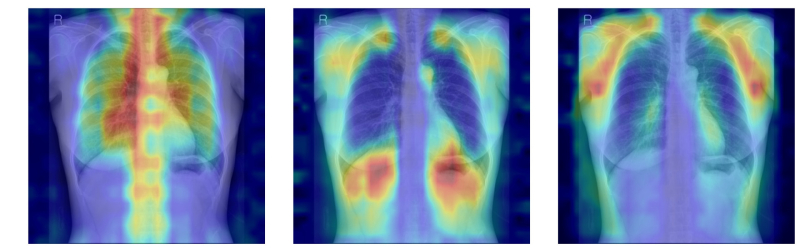

연구팀은 여기에 더해 AI가 실제로 어떤 뼈를 근거로 삼아 판단하는지까지 확인할 수 있도록 ‘설명 가능성’ 평가 체계를 설계했다. 뼈를 모두 가린 상태에서 특정 뼈 부위를 추가해 성능이 얼마나 향상하는지 확인하는 ‘차단 분석 방식(Δbone)’과 Grad-CAM으로 나타난 AI의 주목 영역이 실제 뼈 위치와 얼마나 일치하는지를 계산하는 ‘유의성 지도 방식(IoUbone)’을 통해, AI가 임상적으로 중요한 뼈 구조를 근거로 판단하는지를 정량적으로 검증했다.

그 결과, DINOv2 모델에 LoRA 방식을 적용한 모델이 AUC 0.93(95% CI 0.92–0.94)로 가장 높은 예측 성능을 보였다. 이 모델은 뼈 구조 활용도가 가장 높고, 주목 영역의 타당성에서도 우수해, 예측력과 설명 가능성이 균형 있게 확보된 최적 모델로 평가됐다.